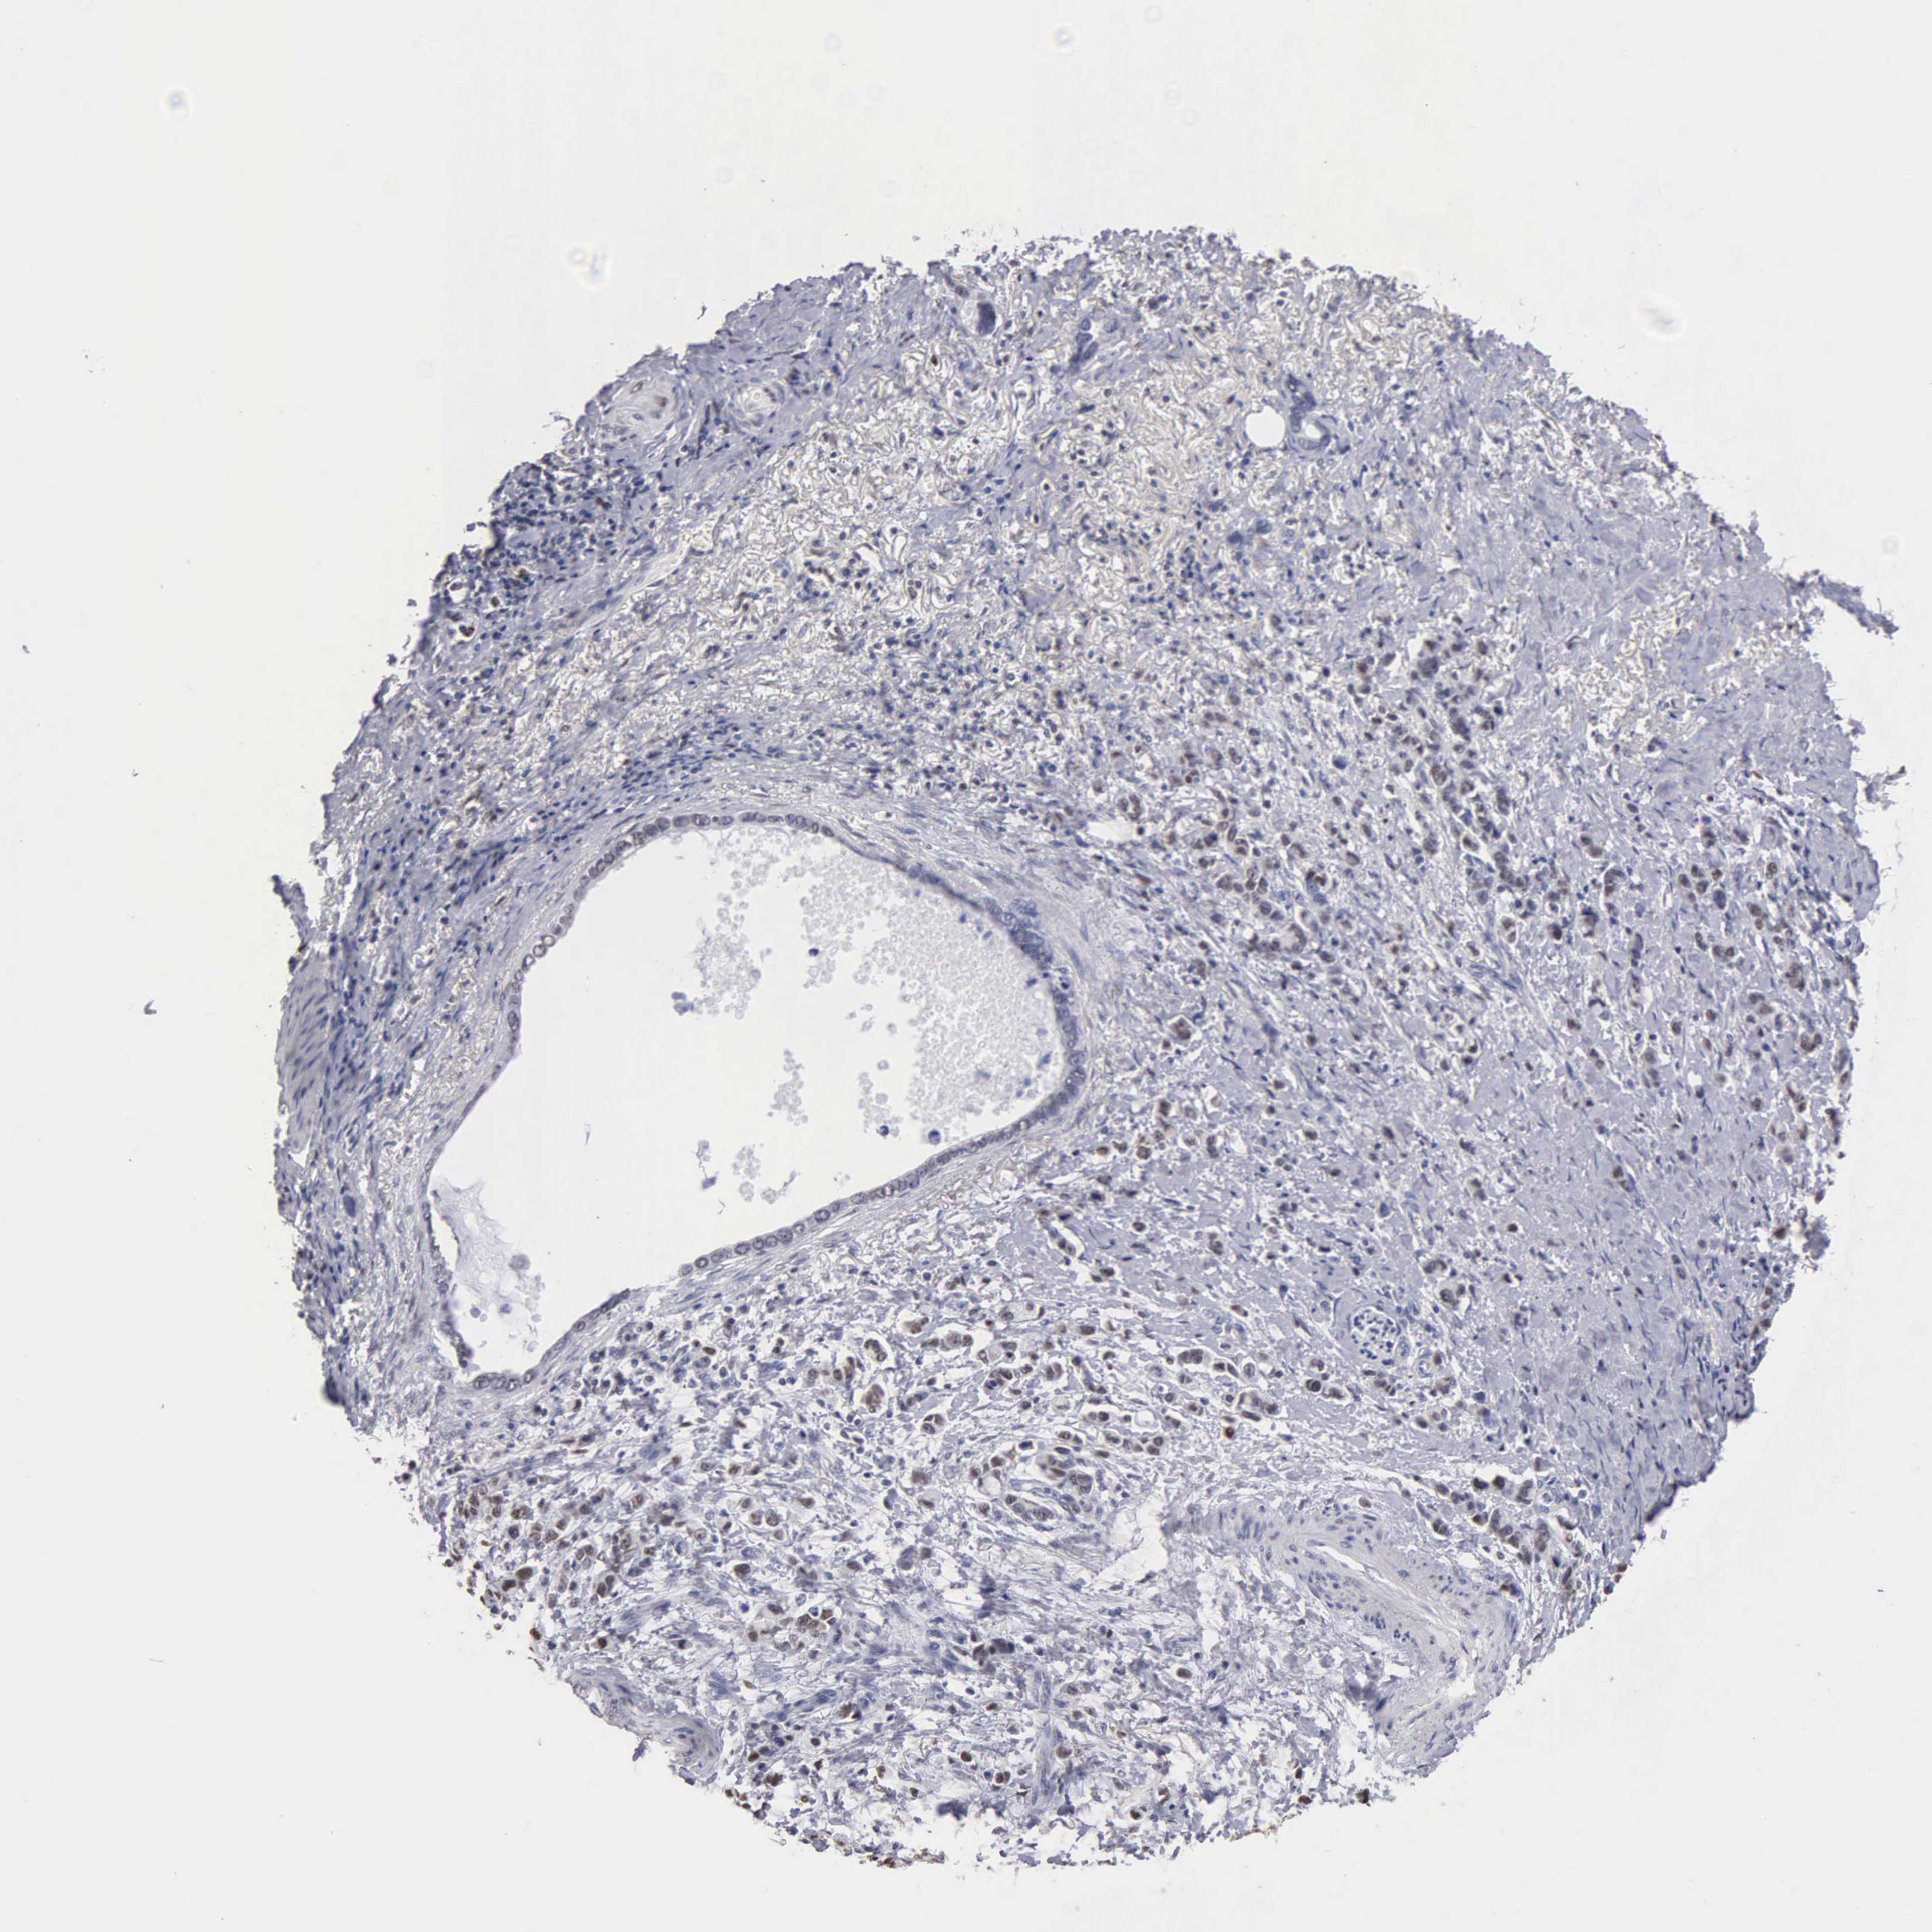

STOMACH CANCER - Protein expressioni

A mouse-over function shows sample information and annotation data. Click on an image to view it in a full screen mode. Samples can be filtered based on level of antibody staining by selecting one or several of the following categories: high, medium, low and not detected. The assay and annotation is described here.

Note that samples used for immunohistochemistry by the Human Protein Atlas do not correspond to samples in the TCGA dataset.

Antibody stainingi

Antibody staining in the annotated cell types in the current human tissue is reported as not detected, low, medium, or high, based on conventional immunohistochemistry profiling in selected tissues. This score is based on the combination of the staining intensity and fraction of stained cells.

Each image is clickable and will lead to virtual microscopy that enables deeper exploration of all samples and also displays staining intensity scores, fraction scores and subcellular localization as well as patient and tissue information for each sample.

Antibody CAB000350

Staining

High

Medium

Low

Not detected

Intensity

Strong

Moderate

Weak

Negative

Quantity

>75%

75%-25%

<25%

None

Location

Nuclear

Cytoplasmic/membranous

Cytoplasmic/membranous,nuclear

Adenocarcinoma, NOS